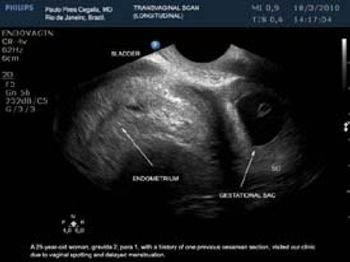

This is a confirmed case of scar ectopic pregnancy. Yesterday, I carried out this exam in an emergency room, without much time to perform an adequate sonogram, the patient did not feel good with “cramps” but no signs of bleeding.

Implantation in the scar of a previous Cesarean is thought to be the rarest of ectopic pregnancies. With the increasing numbers of Cesareans performed, scar implantation may become more frequent as well. We present an illustrative case.